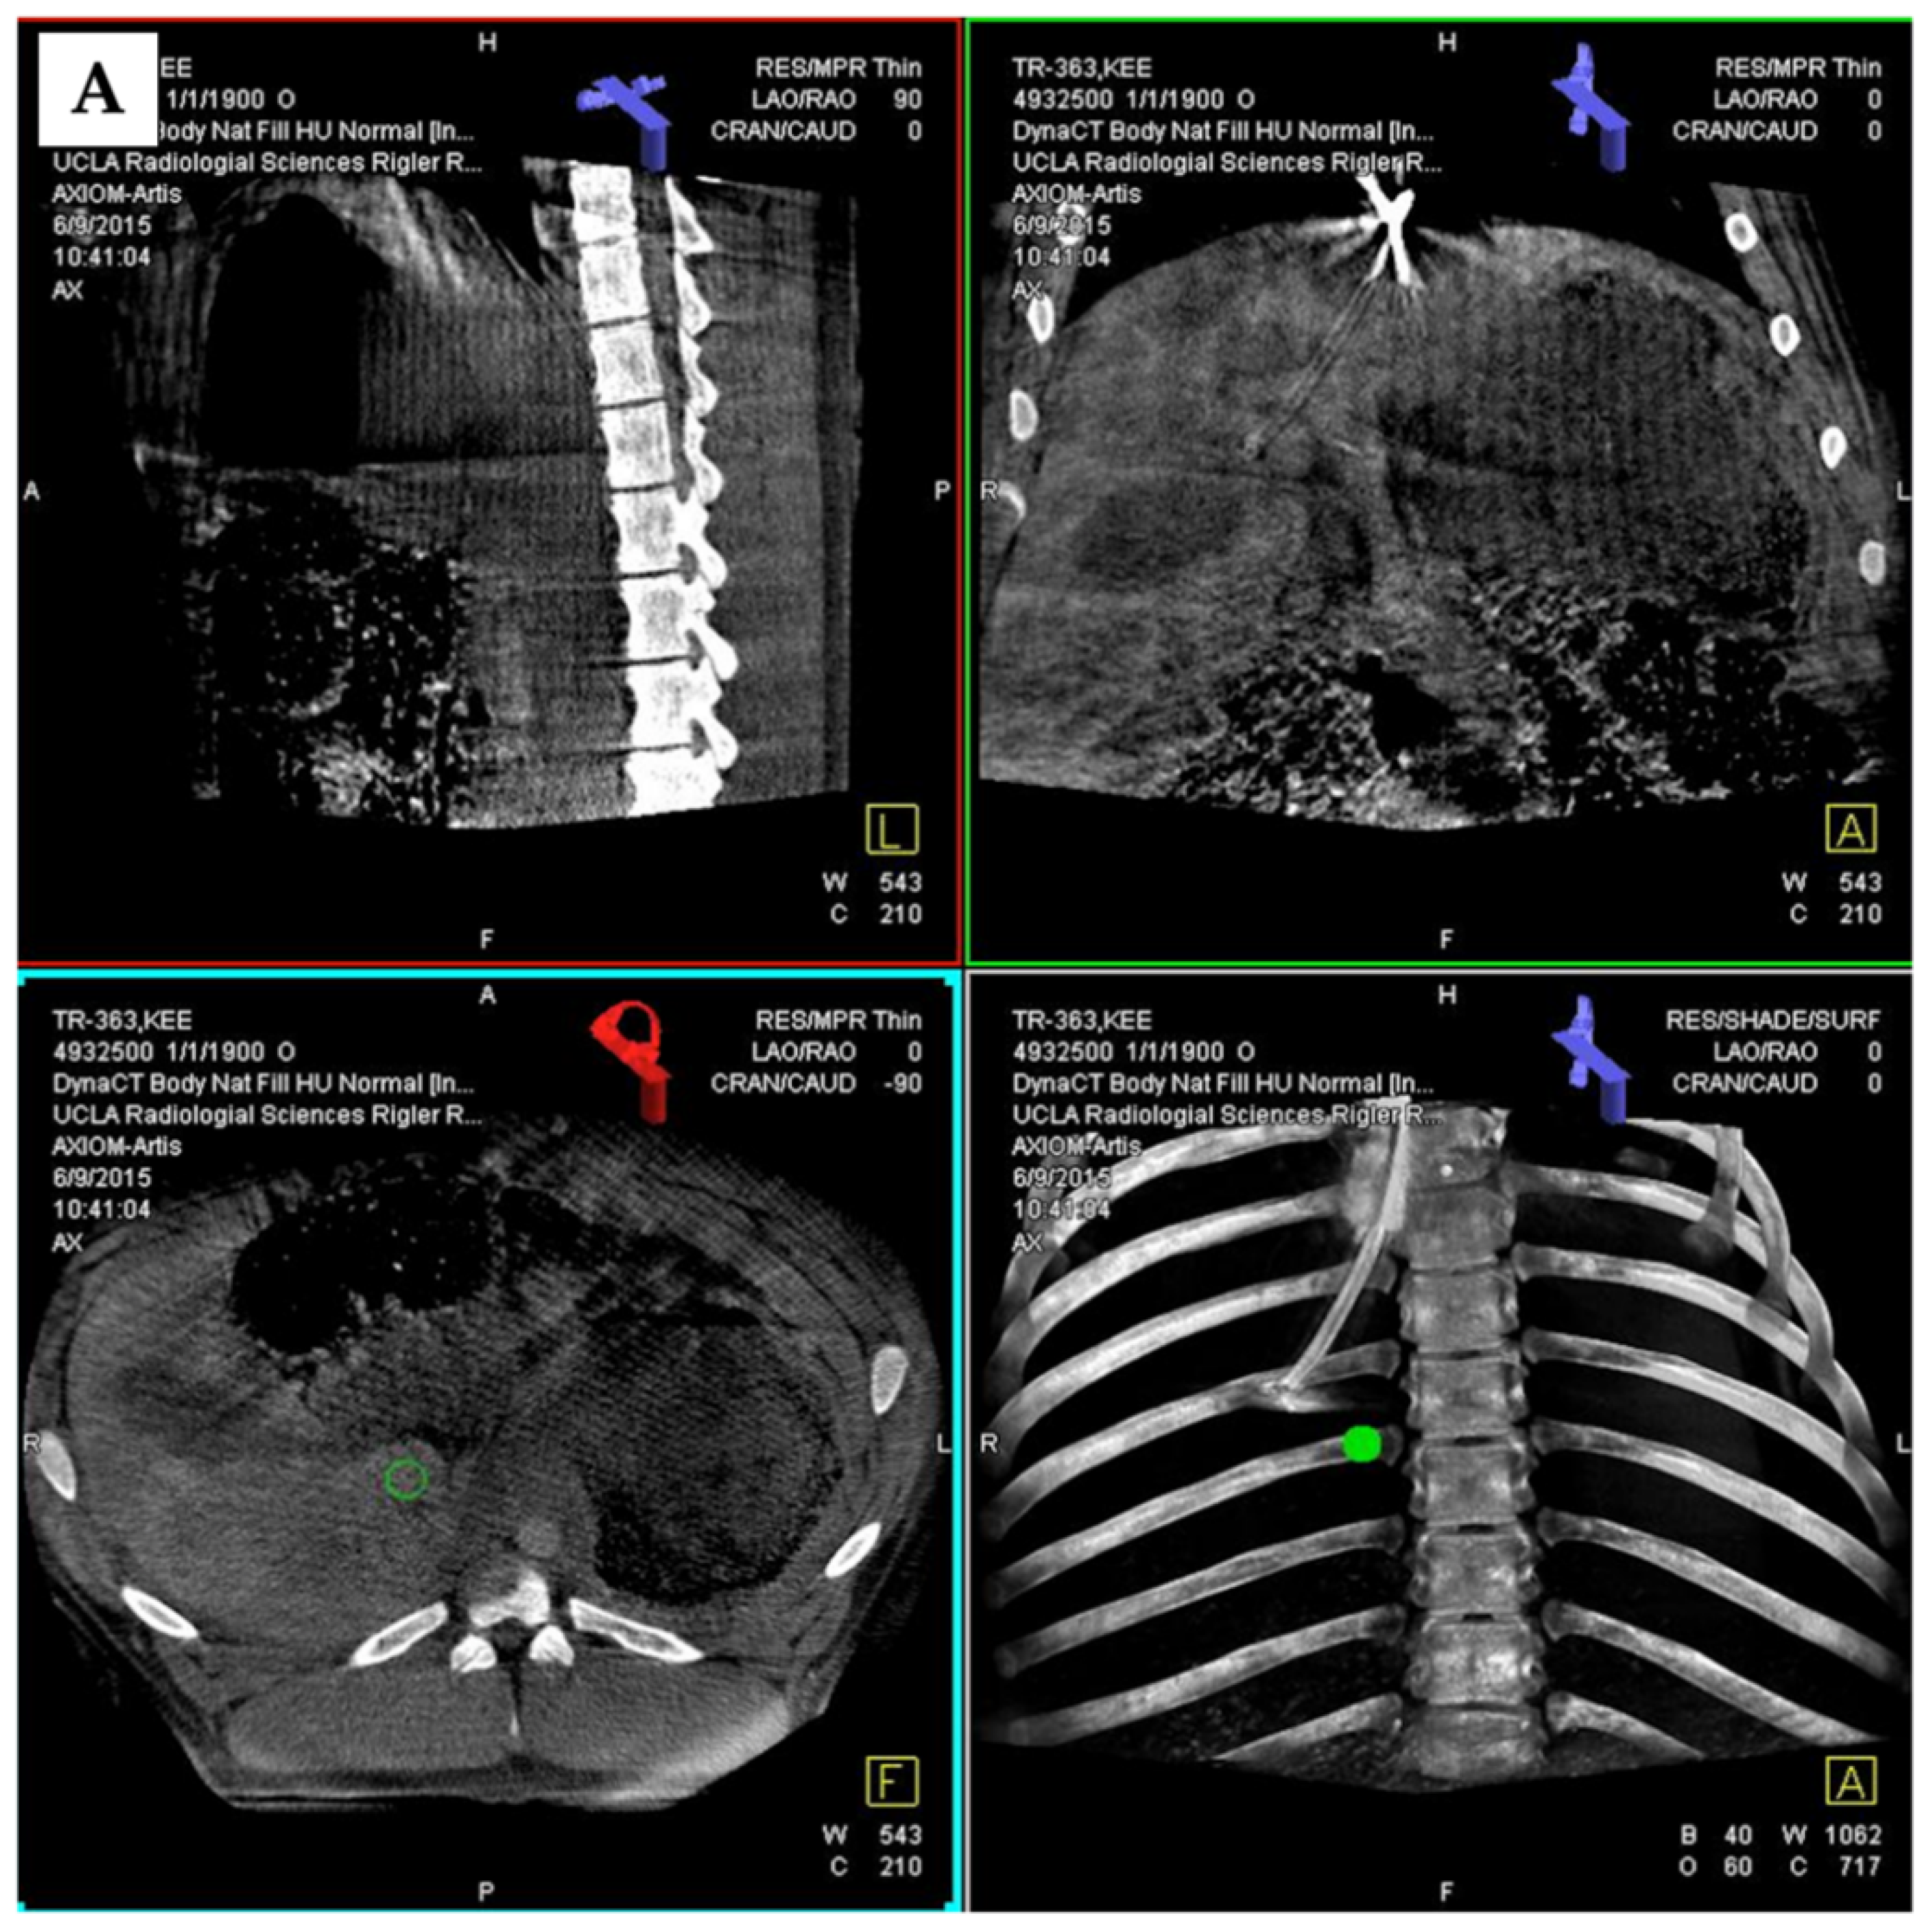

3.3. 3D Angiography-Guided TIPS Using CBCT/Angiography-Fused Images